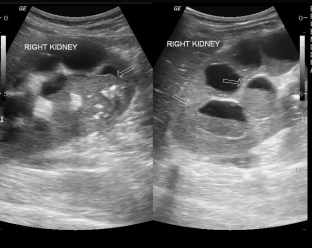

- ultrasound examination: the kidney is enlarged, has uneven contours, echo-negative formations of various sizes with echostructural inclusions due to purulent contents are observed;